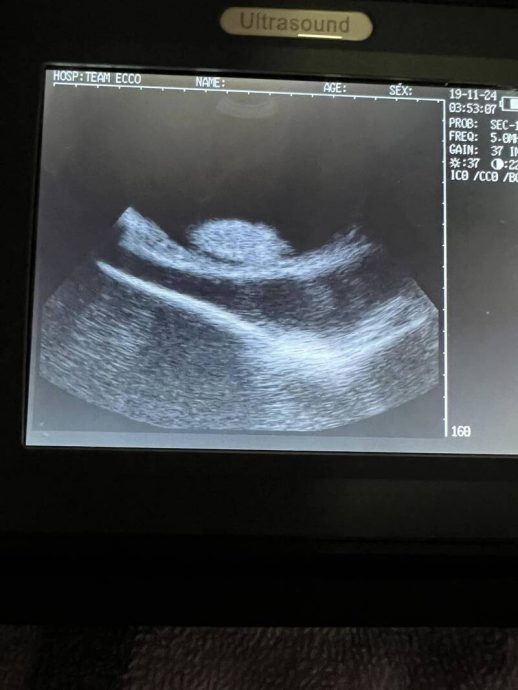

美媒《纽约邮报》报道,北卡州亨德森维尔的ECCO团队水族馆与鲨鱼研究室透露,夏洛特从去年9月开始体内出现肿胀,原本还以为是恶性肿瘤,没想到竟然是怀孕了。

水族馆方面认为,夏洛特怀孕有两种可能,第一种就是“孤雌生殖”,亦即卵子无需受精即可自行发育;至于第二种,则是水族馆去年7月曾将两条一岁大的条纹斑竹鲨和夏洛特养在一起,后来发现夏洛特身上有数道咬痕,这是鲨鱼进行交配所留下的标志痕迹,条纹斑竹鲨和魟鱼都属于软骨鱼纲。

水族馆创办人拉默尔透露,夏洛特体内最多孕育着4条魟鱼宝宝,等到出生后进行DNA检测就可解开谜题。美国网友看到这则消息后纷纷留言当爹,有人直说:“我承认就是我,那天天色已晚,我一直在喝酒,然后她(夏洛特)突然向我拍动她性感的胸鳍,就像是充满欲望的水中舞蹈,我真的无法抗拒爱情的诱惑。”(自由时报)